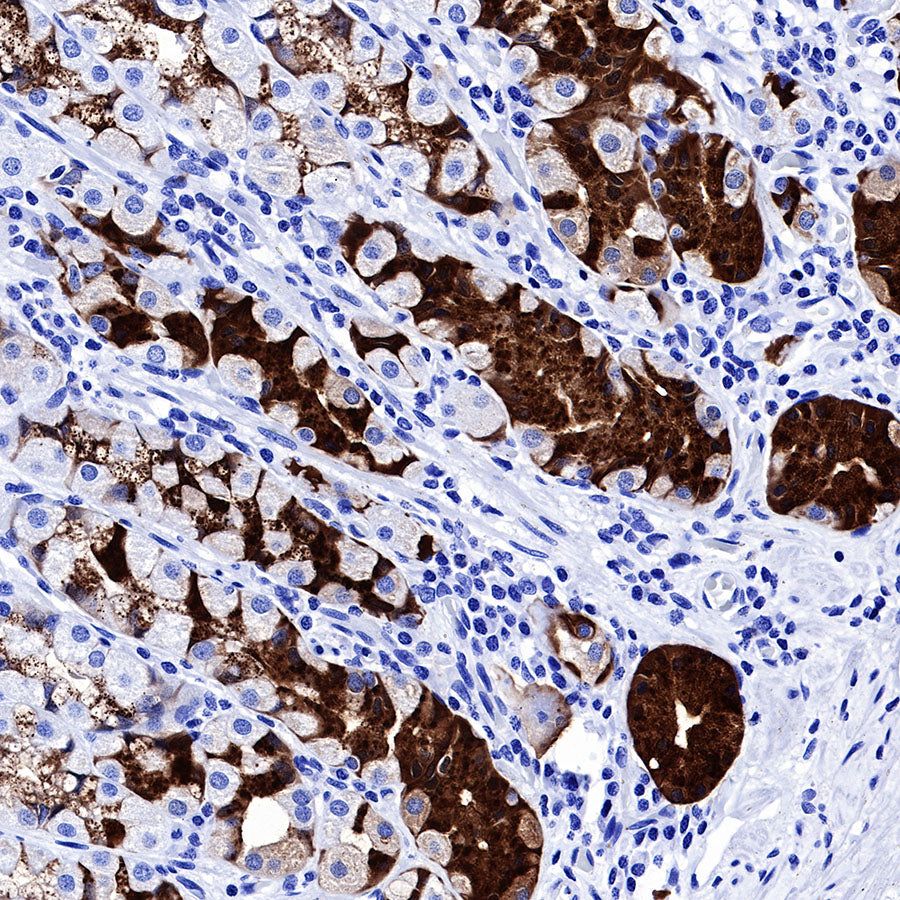

IHC shows positive staining in paraffin-embedded human stomach. Anti-PG II/PGC antibody was used at 1/1000 dilution, followed by a HRP Polymer for Mouse & Rabbit IgG (ready to use). Counterstained with hematoxylin. Heat mediated antigen retrieval with Tris/EDTA buffer pH9.0 was performed before commencing with IHC staining protocol.